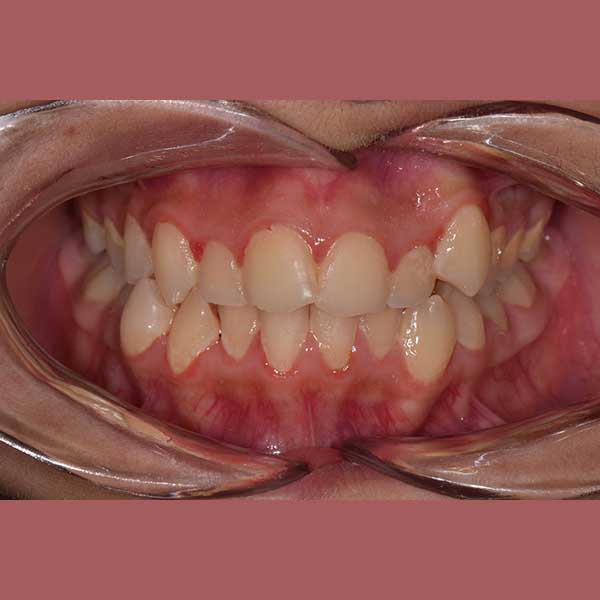

AFTER

راجعتني هذه الشابة وهي تعاني من تراكب شديد في أسنانها العلوية والسفلية. المشكلة الأبرز كانت عدم وجود مسافة كافية لنابها العلوي الأيسر، مما أدى لبقائه مرتفعاً وبارزاً. كما كان الازدحام في الأسنان السفلية يسبب لها صعوبة في التنظيف وتراكماً سريعاً للجير.

بعد دراسة دقيقة للحالة، قرر الدكتور خالد الكاتب أن العلاج ممكن بالكامل بدون قلع أي أسنان. تم الاعتماد على تقويم الدايمون (ذاتي الربط)، والذي يشتهر بقدرته على توسيع الفكين بفعالية وتوفير المسافة اللازمة لرصف الأسنان وإنزال الناب المرتفع إلى مكانه الصحيح.

كما تظهر الصور، تم حل مشكلة الازدحام بالكامل وتم رصف جميع الأسنان بشكل مثالي. استقر الناب العلوي في مكانه الطبيعي ضمن القوس السني، وأصبحت الأسنان السفلية متراصة وسهلة التنظيف. النتيجة هي ابتسامة جميلة وصحية منحت صديقتنا الشابة الثقة التي تستحقها.